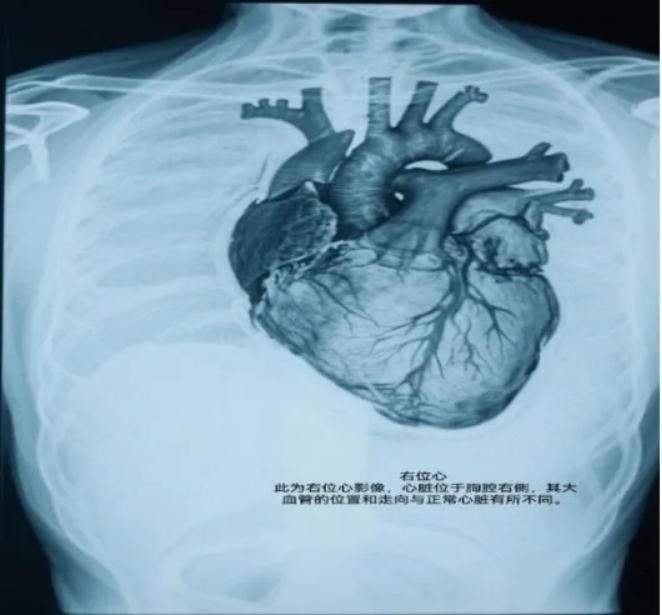

刚新婚不久的军嫂小米(化名)是一位复杂先天性心脏病患者。与常人不同,她出生时仅有一个心房,心脏位置还错位地长在了胸腔右侧,且伴大动脉异位、多根血管异常结构。

小米的这种右位心结构,全球发病率仅约0.05%-0.1%,并且可能导致患者出现反复发生的心力衰竭,而手术是唯一能根治的方法。

右位心,顾名思义,是指心脏的位置在胸腔的右侧,而非通常的左侧,这是一种极为罕见的先天性心脏病。